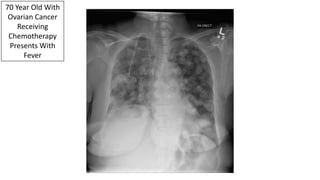

70 Year Old With

Ovarian Cancer

Receiving

Chemotherapy

Presents With

Fever

Diffuse Pulmonary Metastatic Disease